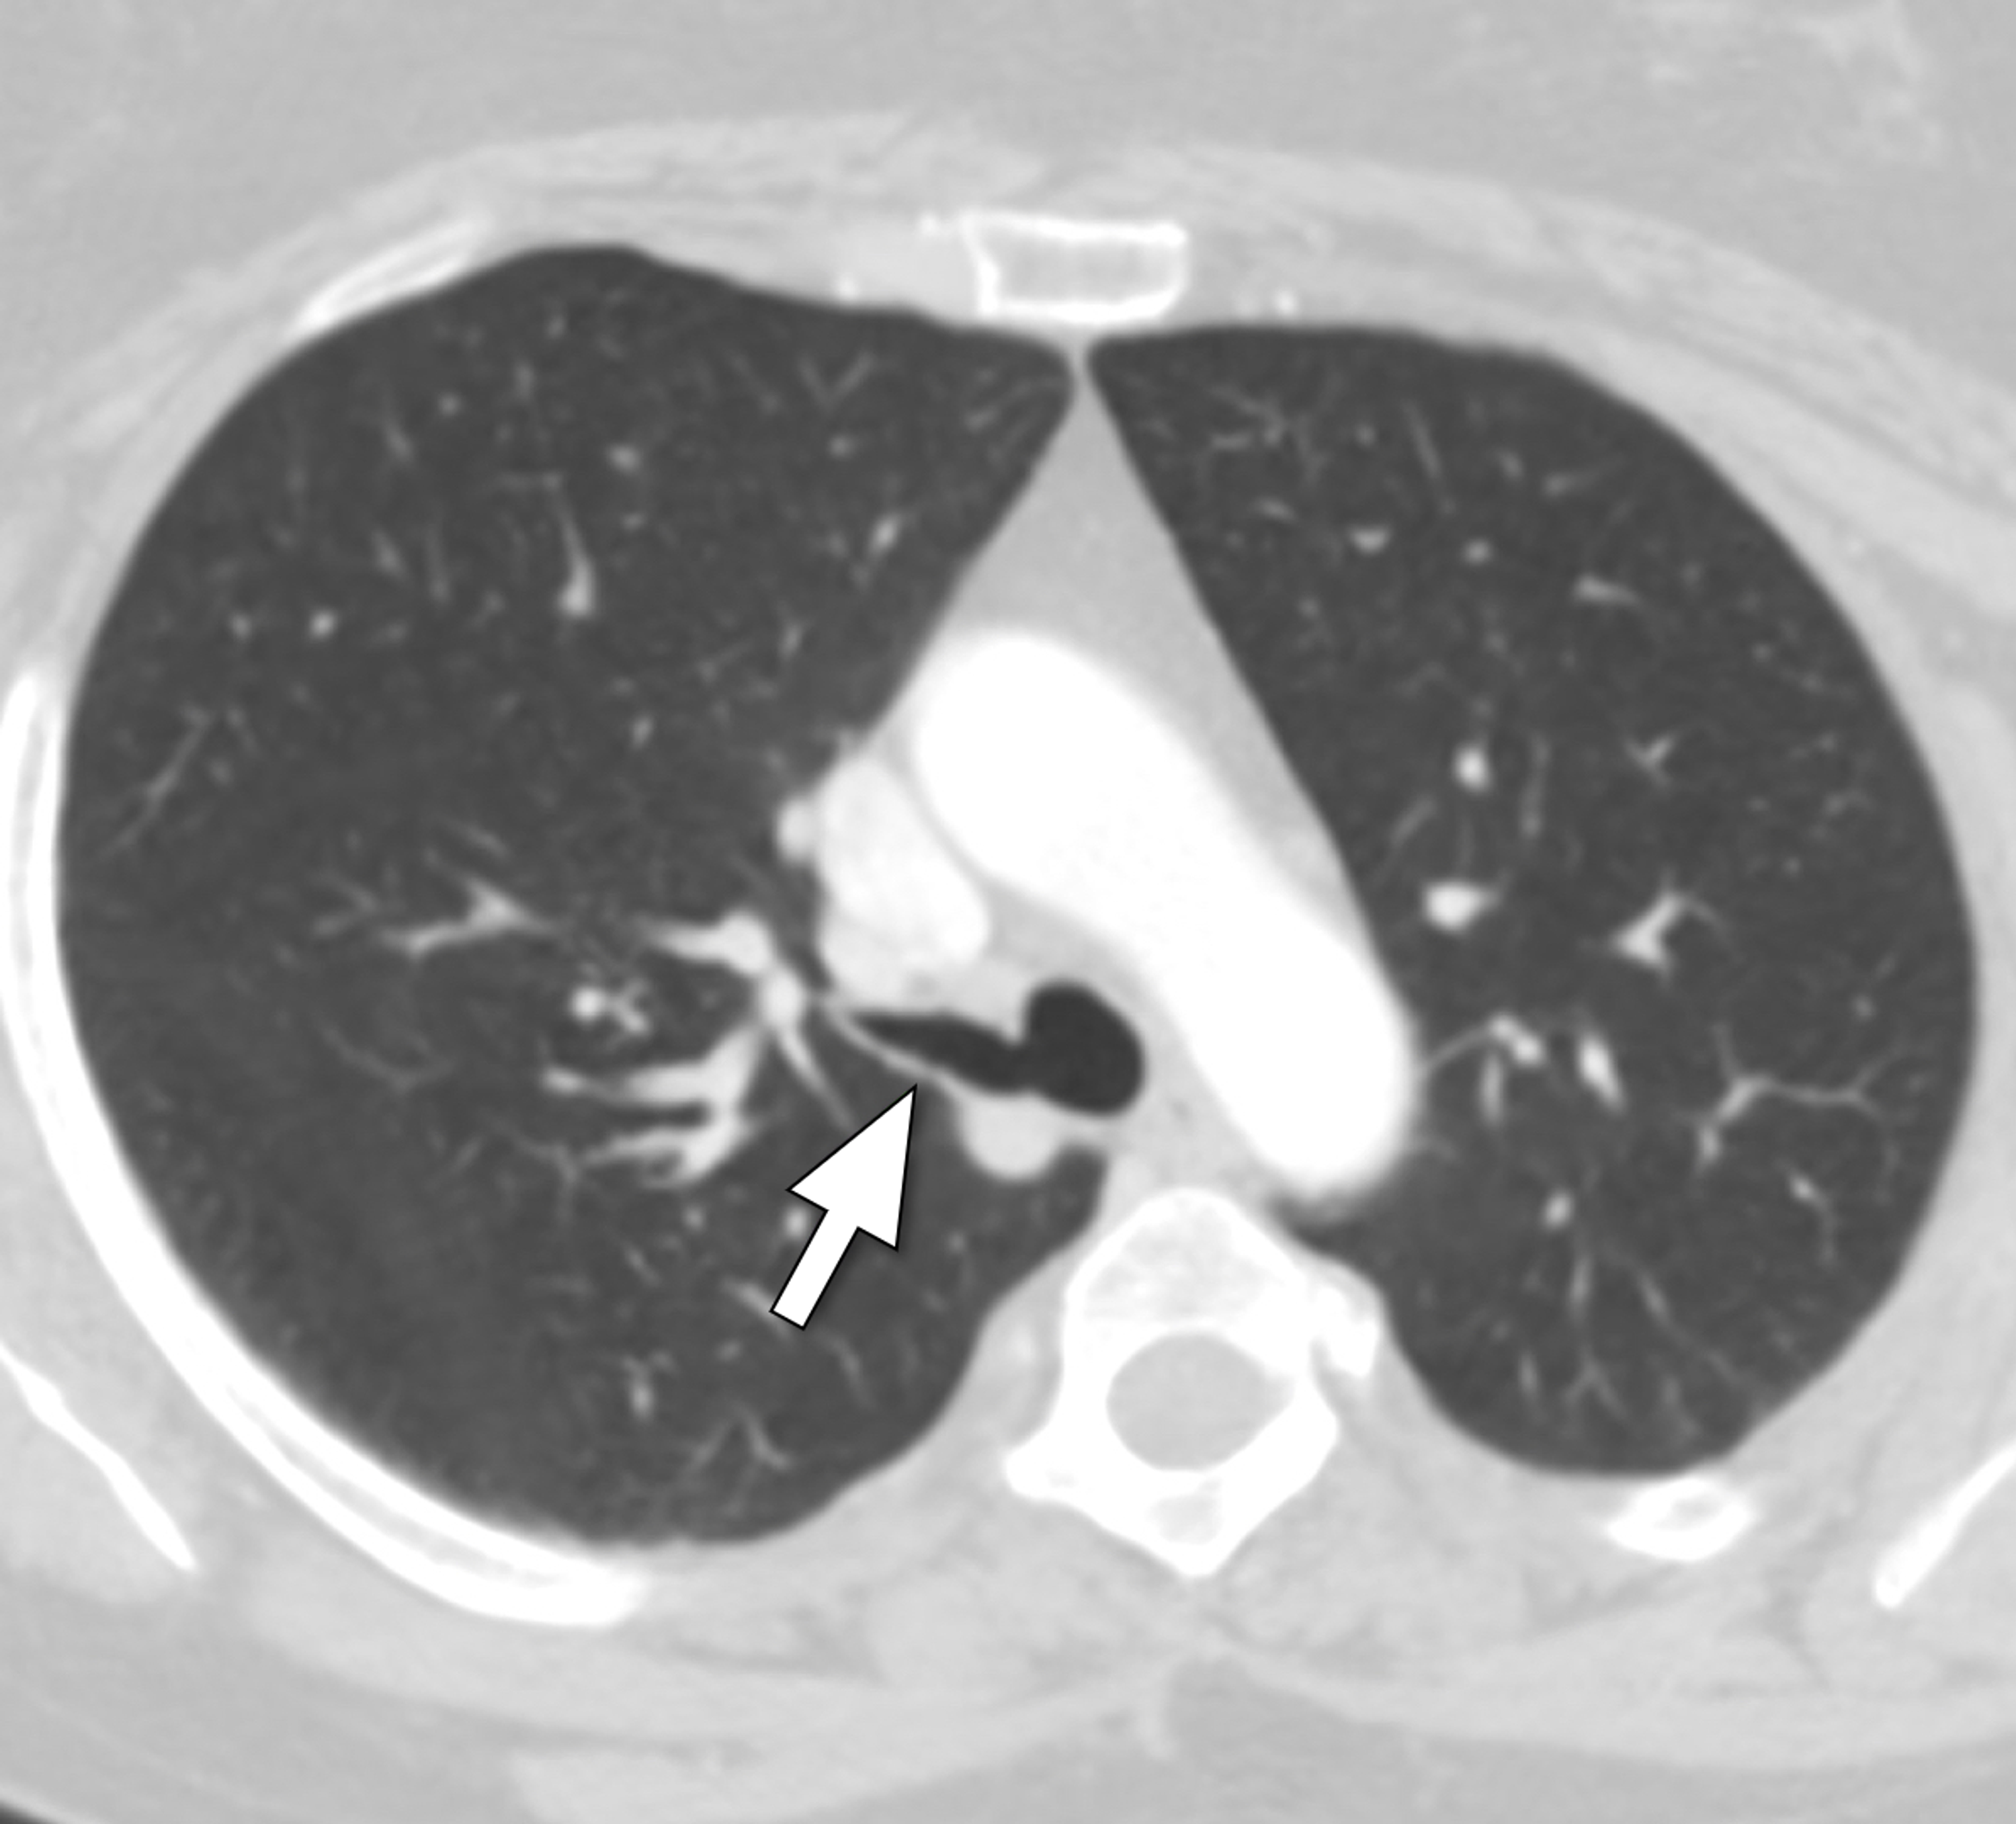

Cureus Tracheal Bronchus A Rare Etiology of Recurrent Pneumonia in Tracheal Pneumonia Our study demonstrated that early tracheostomy placement was not associated with. Timing of tracheostomy placement on overall mortality is a controversial topic in the field. The tracheal bronchus is a rare congenital anomaly described as a collection of bronchial. Tracheal aspirate gram stain & culture. Tracheal Pneumonia.

Tracheal bronchus a rare cause of recurrent pneumonia in adults BMJ Tracheal Pneumonia Tracheal aspirate gram stain & culture. Timing of tracheostomy placement on overall mortality is a controversial topic in the field. The tracheal bronchus is a rare congenital anomaly described as a collection of bronchial. Our study demonstrated that early tracheostomy placement was not associated with. Tracheal Pneumonia.

Cureus Tracheal Bronchus A Rare Etiology of Recurrent Pneumonia in Tracheal Pneumonia The tracheal bronchus is a rare congenital anomaly described as a collection of bronchial. Our study demonstrated that early tracheostomy placement was not associated with. Timing of tracheostomy placement on overall mortality is a controversial topic in the field. Tracheal aspirate gram stain & culture. Tracheal Pneumonia.

(PDF) Tracheal bronchus associated with recurrent pneumonia Tracheal Pneumonia The tracheal bronchus is a rare congenital anomaly described as a collection of bronchial. Tracheal aspirate gram stain & culture. Our study demonstrated that early tracheostomy placement was not associated with. Timing of tracheostomy placement on overall mortality is a controversial topic in the field. Tracheal Pneumonia.